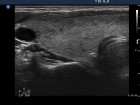

Follow-up examinations (rows from 1st to 8th):

1. The patient initially presented with a large thyroid, therefore we suggested definitive therapy.

2. Note the relation between volume, echogenicity, vascularization and hormone levels.